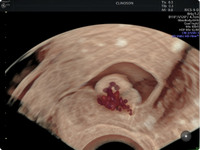

Diagnóstico Avançado de Endometriose

Utilizando equipamentos de última geração e protocolos validados, realizo exames ultrassonográficos altamente detalhados para identificar focos profundos de endometriose, mesmo nos casos mais complexos. Essa abordagem é essencial para definir um plano de tratamento personalizado e eficaz.